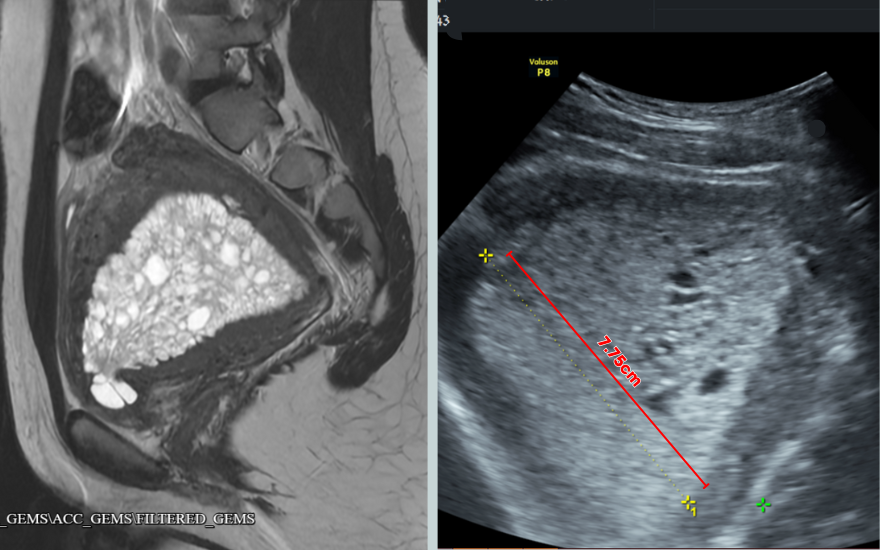

Tại Bệnh viện Đa khoa Hồng Ngọc, thông qua siêu âm, các bác sĩ nhận thấy niêm mạc tử cung của T.A dày đến 7,7cm, gấp 7 lần độ dày thông thường (tử cung của người khỏe mạnh trong những ngày rụng trứng chỉ khoảng 10-12mm).

Niêm mạc tử cung tăng sinh bất thường, dày 7.75cm.

“Mặc dù bệnh nhân còn rất trẻ nhưng khi kiểm tra chúng tôi đã ghi nhận lớp niêm mạc tử cung dày bất thường, thậm chí gần như bịt kín buồng tử cung cùng nhiều polyp nội mạc. Đây là một trong những trường hợp rất hiếm gặp của tăng sinh niêm mạc tử cung, có nguy cơ tiến triển thành ung thư nếu không được xử lý sớm”, ThS.BSCKII Nguyễn Văn Xuyên (Khoa Sản Phụ khoa, BVĐK Hồng Ngọc) cho biết.